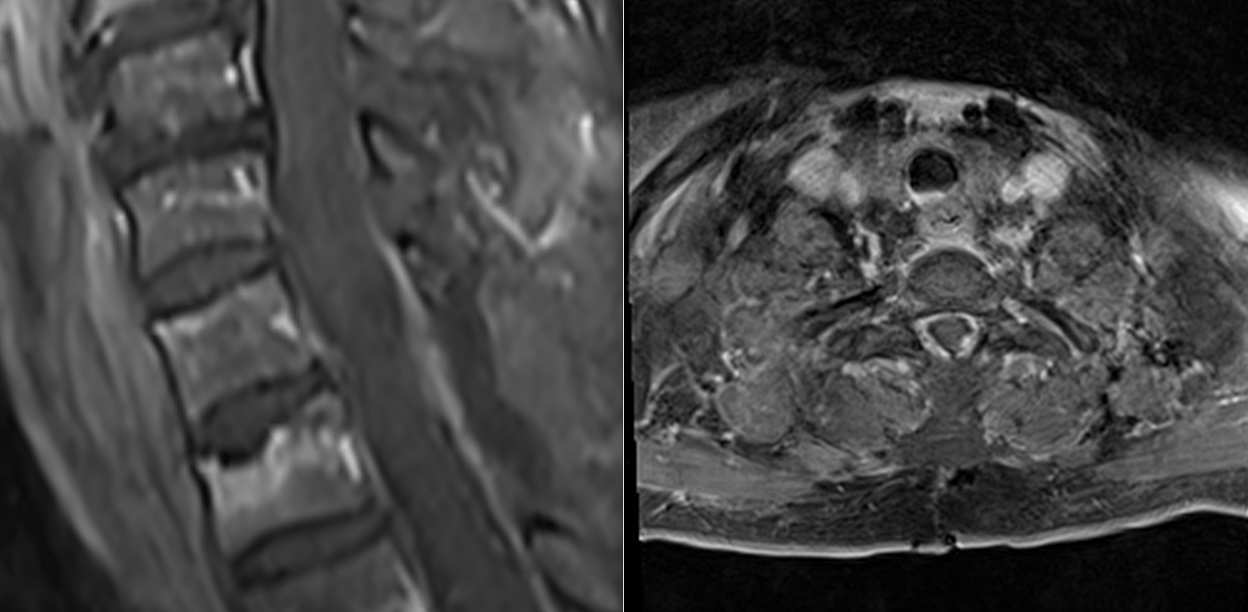

RMN-ul de control postoperator a evidențiat rezecția completă a formațiunii tumorale.

Măduva apare decomprimată, reexpansionată, cu refacerea spațiului lichidian perimedular — un indicator imagistic esențial al succesului chirurgical.

Însă decompresia realizată la timp oferă șansa reală de recuperare funcțională.